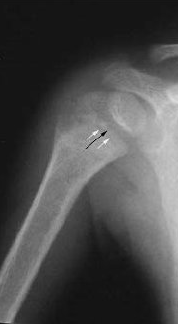

Запитання 28

ПЕРЕЛОМ ЯКОЇ КІСТКИ І В ЯКІЙ ЇЇ ЧАСТИНІ ВИ БАЧИТЕ?

варіанти відповідей

ГОЛОВКИ HUMERUS

ДИСТАЛЬНОГО ЕПІФІЗА HUMERUS

ШИЙКИ FEMUR

ГОЛОВКИ FEMUR

ГОЛОВКИ RADIUS

ПРОКСИМАЛЬНОГО ЕПІФІЗА HUMERUS

ХІРУРГІЧНОЇ ШИЙКИ HUMERUS

АНАТОМІЧНОЇ ШИЙКИ HUMERUS

Запитання 19

РОЗПІЗНАЙТЕ КІСТКУ. ПЕРЕЛОМ ЯКОЇ ЇЇ ЧАСТИНИ ВИ БАЧИТЕ НА РЕНТГЕНОГРАМІ?

ULNA

RADIUS

FEMUR, ШИЙКА

ПРОКСИМАЛЬНОГО ЕПІФІЗА

ДИСТАЛЬНОГО ЕПІФІЗА

ДІАФІЗА

ЛІКТЬОВОГО ВІДРОСТКА

ПРОМЕНЕВОГО ВІДРОСТКА